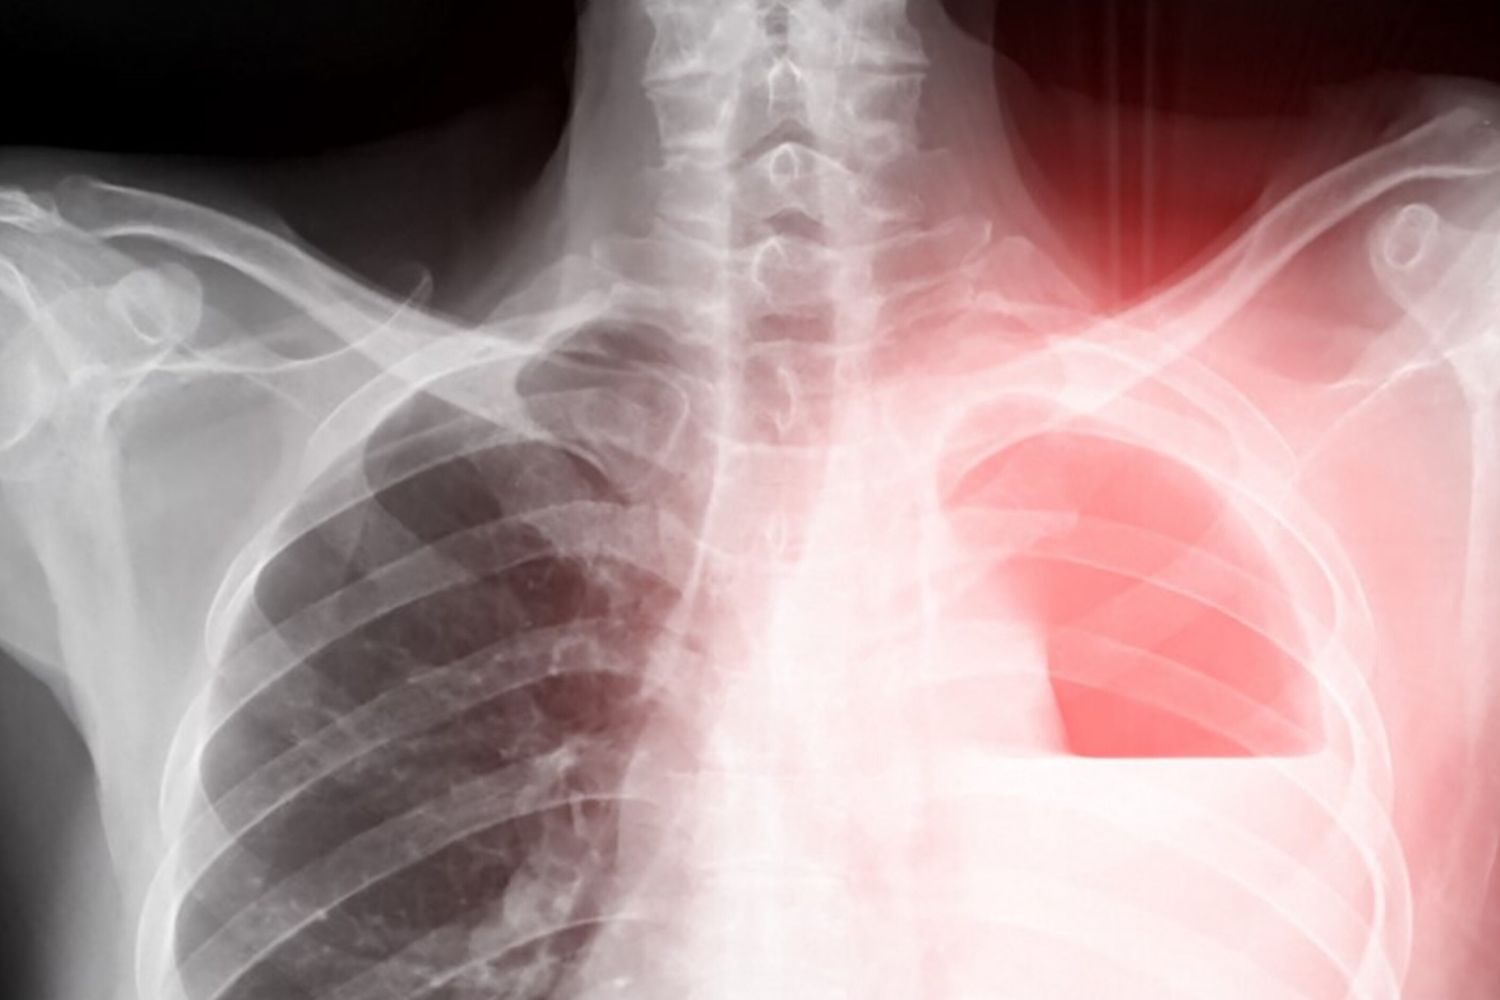

La polmonite bilaterale, che comporta lo stato di infiammazione del tessuto di entrambi i polmoni, infatti è comunemente causata da un'infezione batterica (principalmente Streptococcus pneumoniae, conosciuto anche come pneumococco, ma anche l'Haemophilus influenzae, lo Staphylococcus aureus, la Legionella pneumophila), ma può essere provocata anche da una infezione virale, fungina o dall'aspirazione di un corpo estraneo, e può verificarsi la contemporaneità, come in questo caso, di più agenti infettivi.